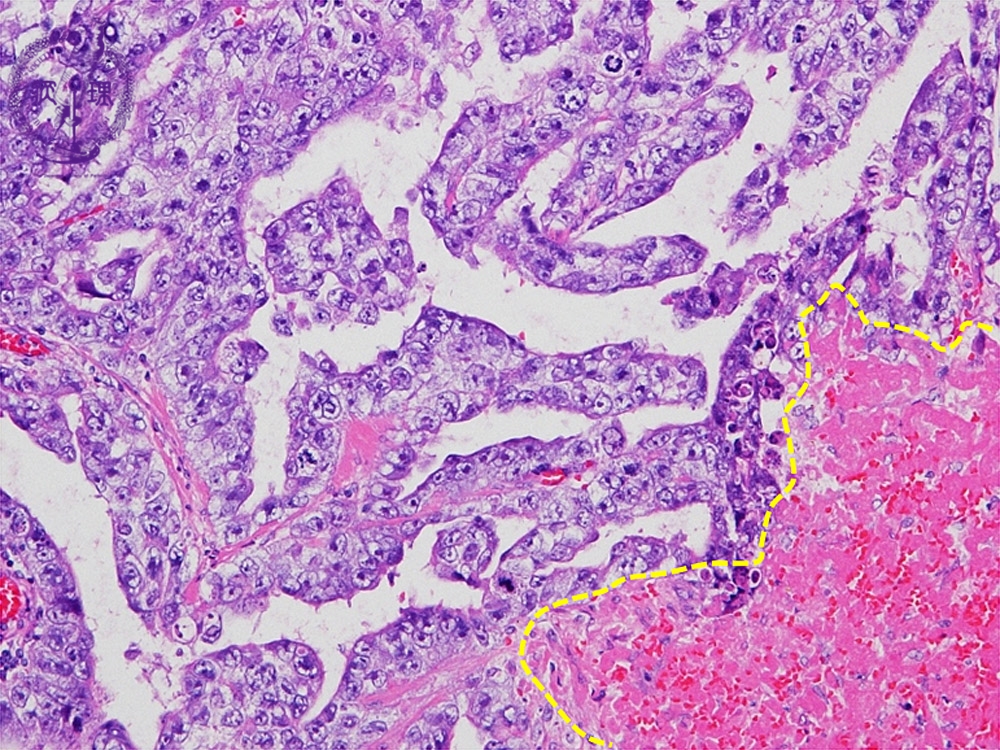

- (5)Embryonal carcinoma

Histology (HE stain, high power): Cuboidal or columnar epithelial tumor cells with severe atypia proliferate in papillary or tubular structure. Hemorrhage and necrosis are seen below yellow dotted line.